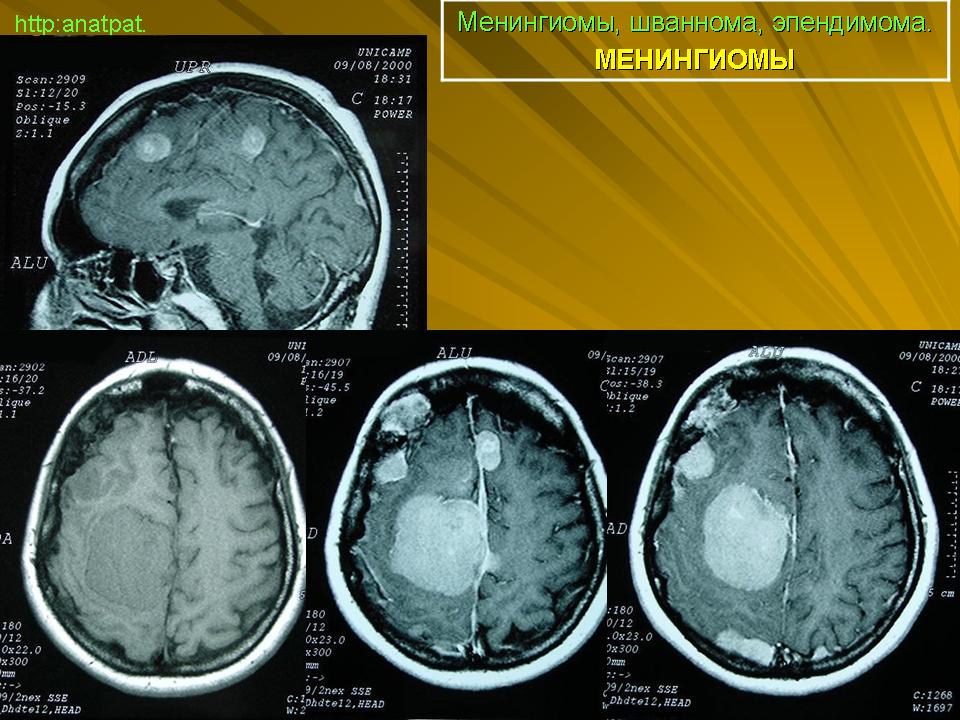

ГМ. Сочетание опухолей. +

Сочетание опухолей.